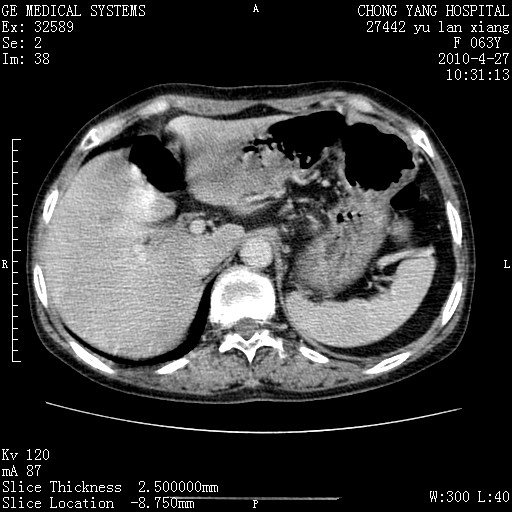

标题: CT26066:F63Y 上腹正中压痛半月,CA199:7400u/ml,MR示胰腺炎伴 [打印本页]

胰腺癌侵犯腹腔动脉干-分支、胃壁、左侧膈肌伴胰周及腹膜后淋巴结转移、胆囊切除术后。

胰腺癌侵犯腹腔动脉干-分支、胃壁、左侧膈肌伴胰周及腹膜后淋巴结转移、胆囊未显影。